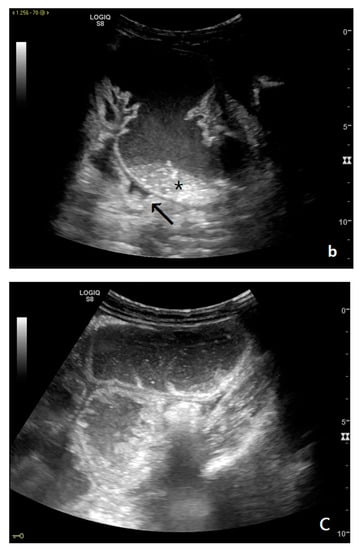

Figure 3.

A decompensated SBO, presenting fluid-filled, dilated small bowel loops with increased parietal thickening (*) (a) and free fluid between bowel loops (a). ‘Caliber jump’: a difference in caliber between the swollen loops upstream (white arrows) (a,b) and the collapsed loops downstream of the obstruction (black arrows) (a,b).

The persistence of obstruction causes an increase in endoluminal pressure, and the liquid content normally present in the intestinal lumen cannot be reabsorbed. Bowel layers act as a sponge, determining the passage of fluid in the peritoneal cavity (Figure 3a,b). In the initial phase, the liquid is disposed between the recesses of the mesenteric fan, giving rise to the characteristic ‘sign of the thong’ [39]. With the persistence of the obstruction, the amount of free fluid increases, and it can be found in the abdominal cavity. The presence of free fluid is directly correlated to bowel parietal vascular alterations [13,37,40,41].

Parietal changes are characterized by the presence or absence of parietal and valvulae conniventes thickening and parietal wall stratification. The evaluation of parietal changes follows a dichotomic diagnostic process based on the reference values (normal thickness 1–3 mm, wall thickening >3 mm, thinned walls <1 mm): thickened walls/valvulae conniventes (YES/NO) or thinned walls (YES/NO) (Figure 3a,b) [29,30,35]. Although ultrasound allows us to identify the five concentric layers of the intestinal loops, this evaluation is not applied in the diagnosis of SBO. In practice, the evaluation is limited to the presence or absence of parietal stratification (two-layer double halo sign or three-layer target sign) (Figure 4a–d and Figure 5a,b) [29,35,42].